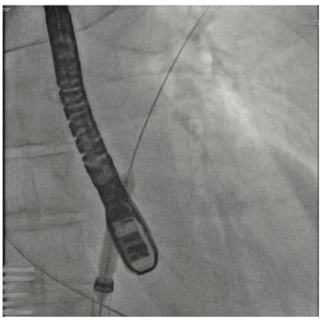

An 80-year-old female with a history of heart failure with reduced ejection fraction, hypertension, and chronic kidney disease presented with worsening dyspnea and fatigue for 6 months despite being on optimal guideline-directed medical...